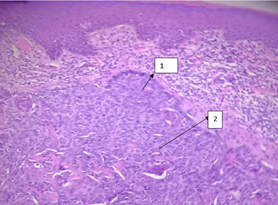

A 58-year-old patient without comorbidities began suffering due to self-detection of a vulvar nodule with pain and bleeding, with menarche at 12 years of age, menopause at 48 years of age, without hormone replacement, and negative cervical screening. Exploration showed a 1cm nodular lesion in the upper third of the right labia majora, rough, regular edges, erythematous, without color changes on acupressure, non-painful, fixed to superficial planes, without adjacent lesions. Radical local excision was performed and the histopathological study reported basal cell carcinoma (Figure 1) (Figure 2). Extension studies without evidence of pelvic or inguinal lymph node activity by tomography. During the 2-year follow-up, she has not presented recurrence.

Figure 1 Basel cell carcinoma of the vulva. (1) cells with a basaloid appearance, are characterized by a basophil nucleus, little cytoplasm, little and isolated mitoses, the cellular nests are arrangeed in a palized. (2). Little stroma retracts forming spaces (claves).